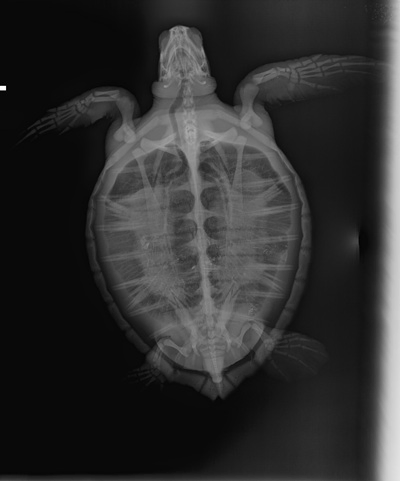

4.2 lbs. non-FP Atlantic Green

Slight swelling of the neck, minor abrasions on carapace, and minor bruising on plastron